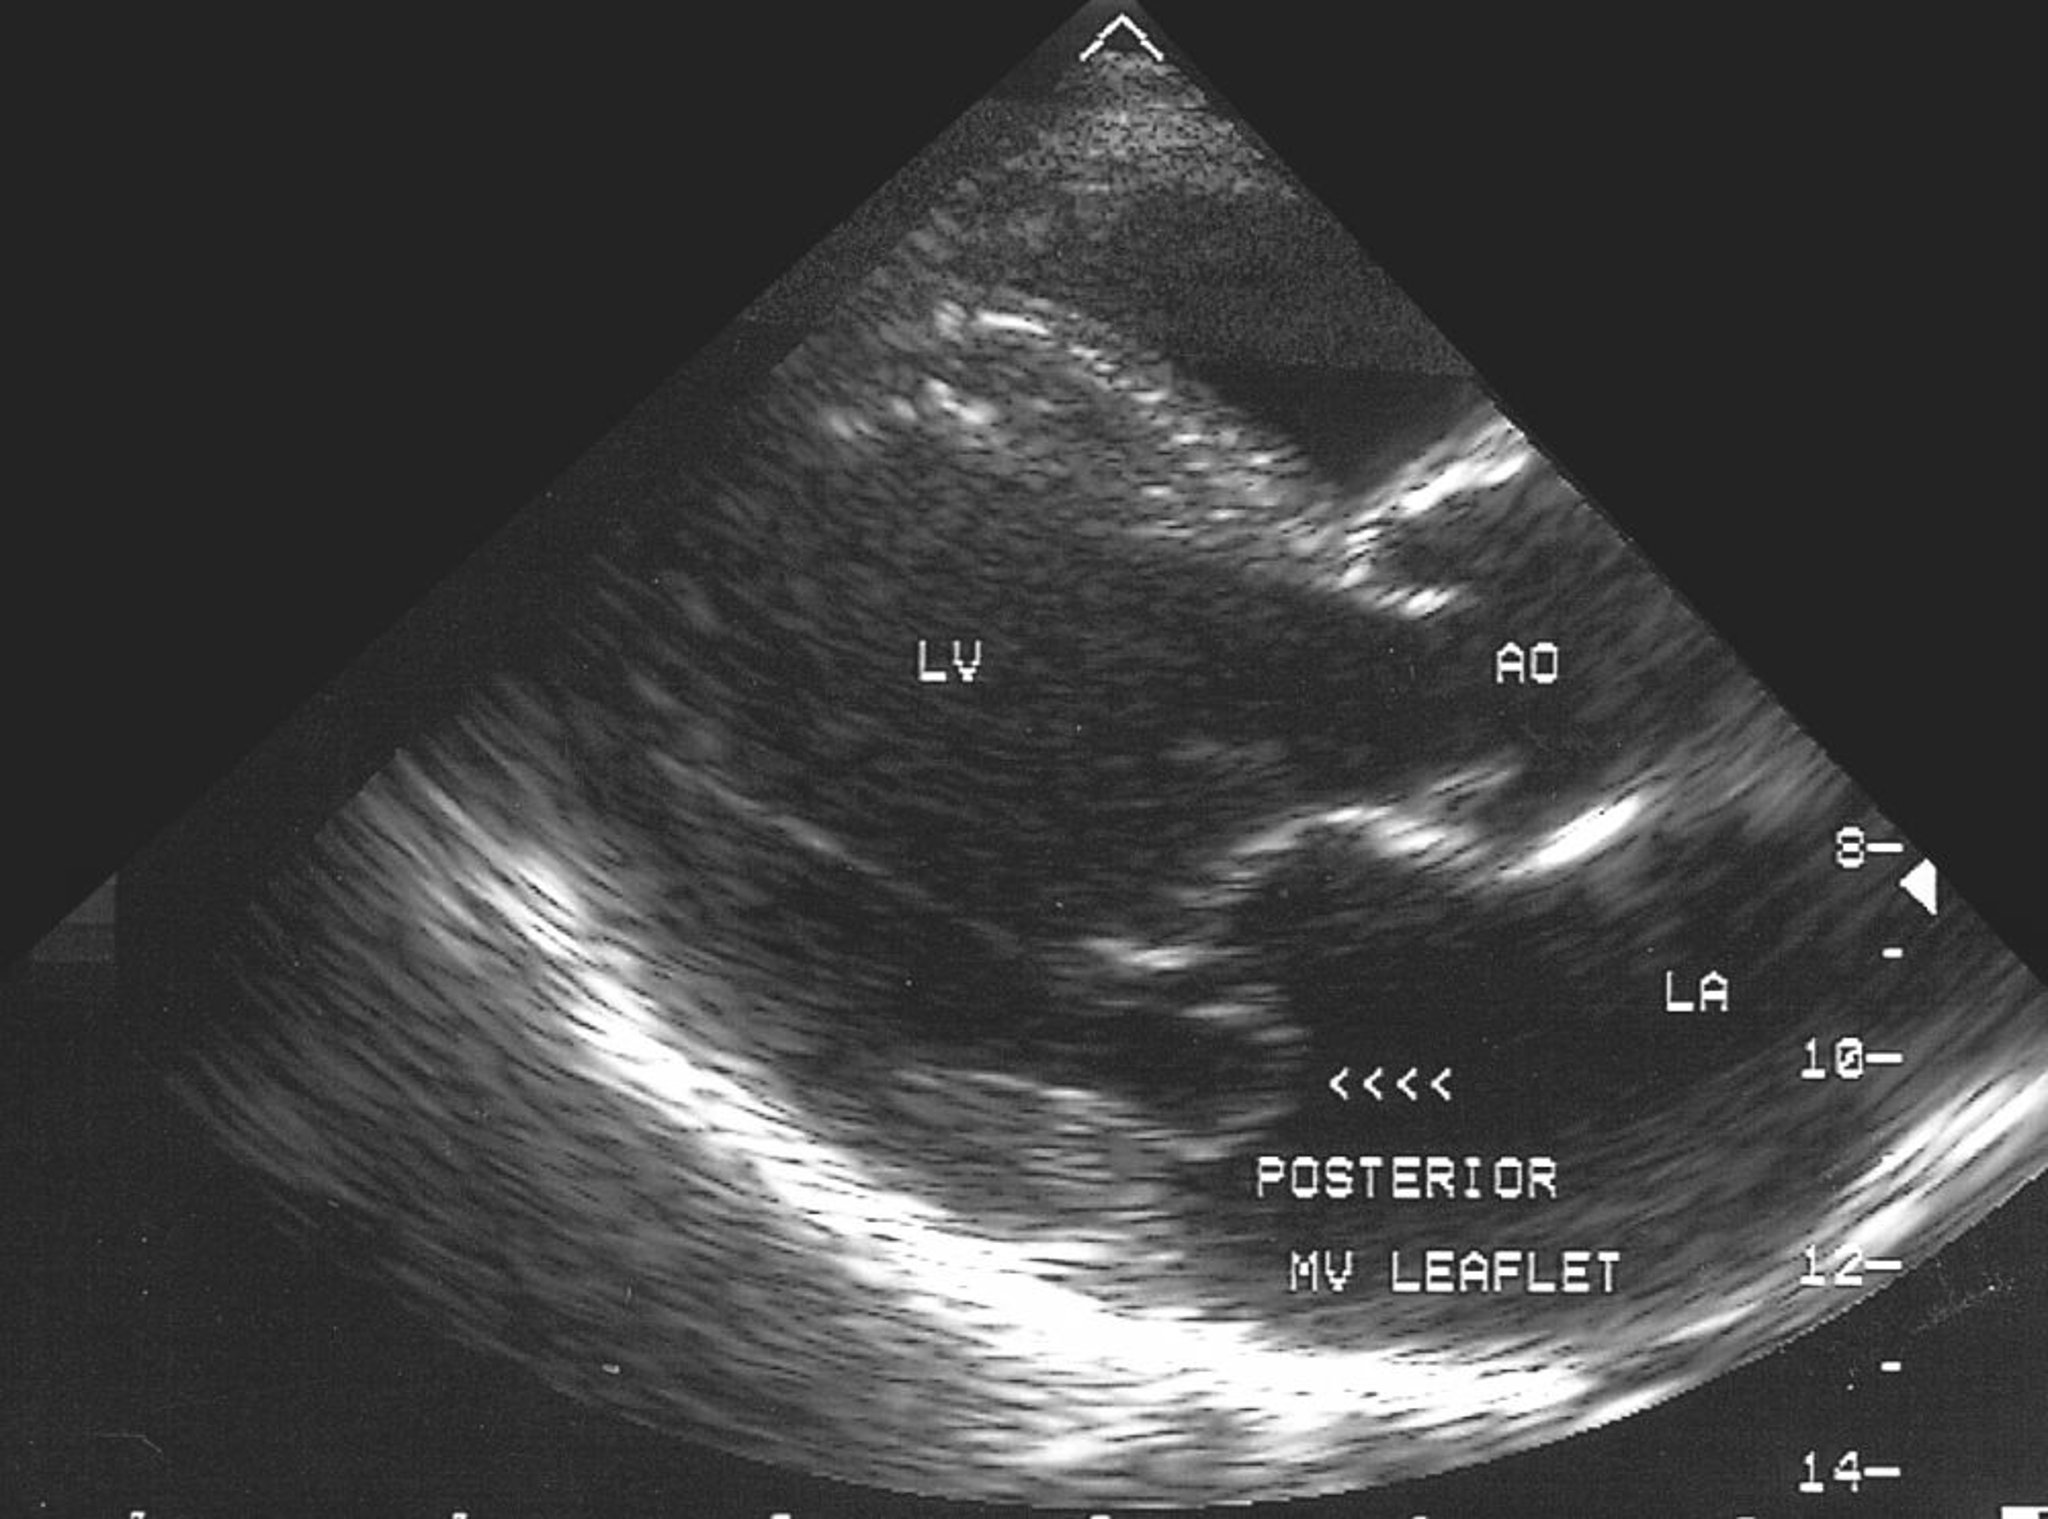

Mitral Valve Prolapse (Echocardiogram)

This echocardiographic image shows prolapse of the posterior leaflet of the mitral valve into the left atrium (LA).